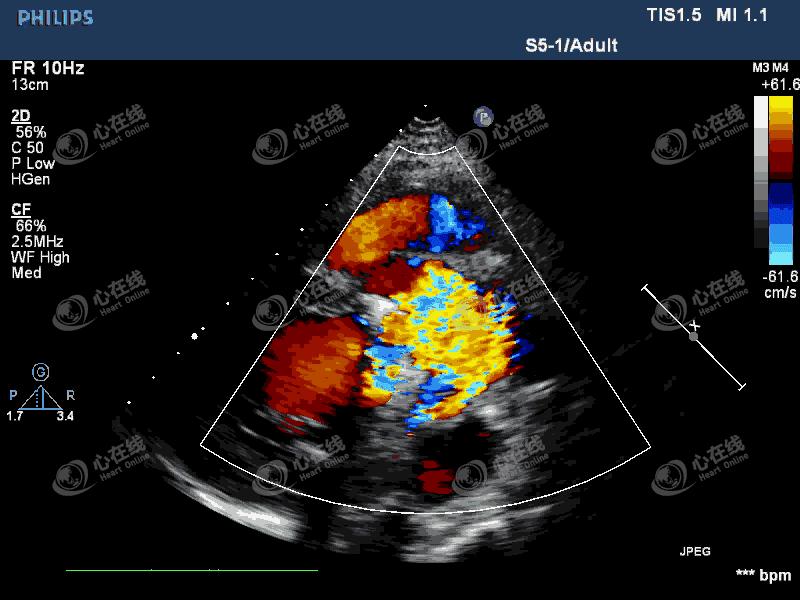

图2 左室长轴切面:彩色多普勒示,机械瓣瓣环外侧可见中量血流信号进入左室,另可见机械瓣中心性反流信号。主动脉根部膜样回声破口处可见血流信号,来自主动脉,并穿梭于该无回声区内。

图3 四腔心切面:彩色多普勒显示中量偏心性反流信号,起自主动脉瓣机械瓣环外侧。